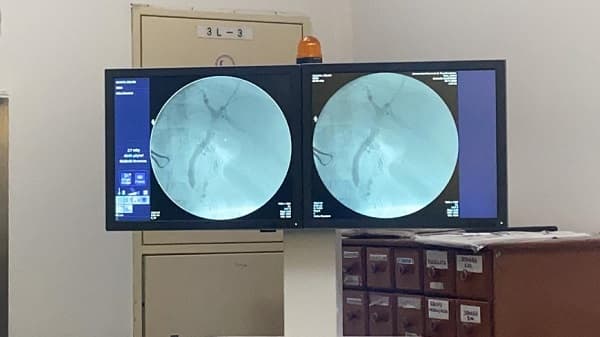

En el Hospital de Clínicas de la Facultad de Ciencias Médicas de la Universidad Nacional de Asunción (UNA) fue realizado un exitoso trasplante renal. El procedimiento se desarrolló en los pabellones quirúrgicos centrales del hospital escuela, con donante cadavérico. Se trata de la cirugía número 163 de esta índole, desde la reactivación de intervenciones desde el año 2014, informó Telefuturo. La familia que sufrió la pérdida de un ser querido apostó a dar vida decidiendo donar el órgano a una mujer de 52 años. La misma padece enfermedad renal crónica y recibe diálisis cada tres semanas hace tres años. De la cirugía participaron neurólogos, anestesiólogos, cirujanos vasculares, urólogos, instrumentadores quirúrgicos, licenciados en Enfermería de Nefrología, cita el reporte. En un video compartido se observa la llegada del órgano en un contenedor, trasladado por un profesional, al citado centro médico, pues la ablación fue realizada en el Hospital de Trauma.